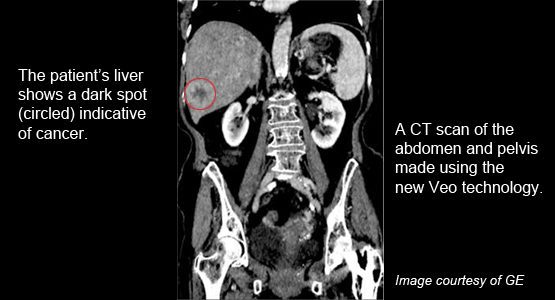

New technology allows CT scans to be done with a fraction of the conventional radiation dose

“We’re excited to be adding Veo to the measures we already have in place to ensure that we get diagnostic images using the lowest amount of radiation possible.”

Using data science to achieve ultra-low dose CT image reconstruction

Ultra-low dose CT scans that provide superior image quality could not only benefit patients, but they could open up entirely new clinical applications.